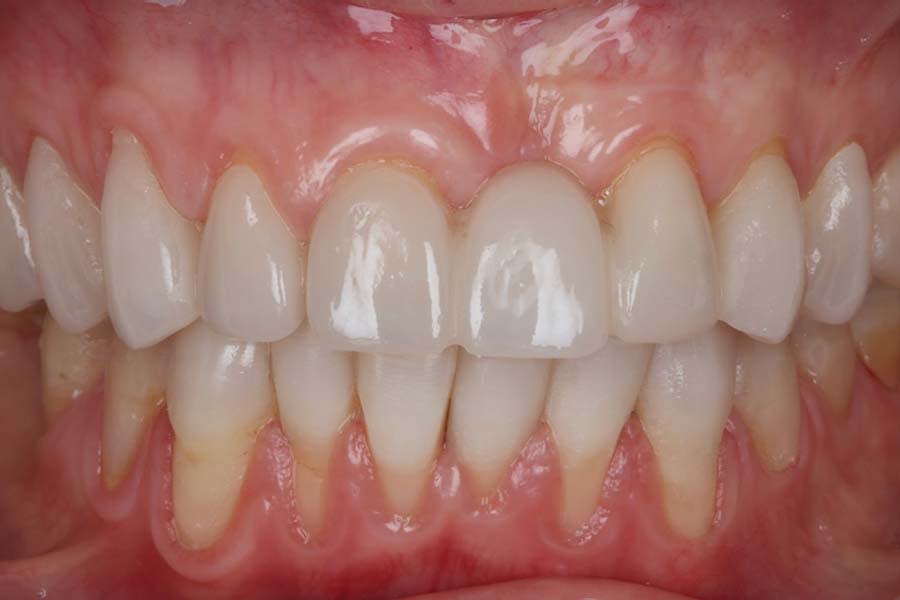

Definitive digital scans of each arch were obtained (Figure 7 and Figure 8), and the definitive restorations were designed based on the diagnostic wax-up (Figure 9). The design files were then exported in standard tessellation language (STL) format and transferred to the in-house technicians for milling of the definitive restorations in lithium-disilicate material. The restorations were subsequently custom-stained and glazed (Figure 10). Based on the patient’s esthetic preferences, modifications were made to the maxillary anterior design before delivery. The definitive restorations were evaluated intraorally and bonded with a luting composite (soft white shade) (Variolink® Esthetic LC, Ivoclar) (Figure 11), with all excess cement carefully removed (Figure 12 and Figure 13). The mandibular incisors were restored with direct composite, and abrasion lesions in the esthetic zone, intended for future root coverage, were provisionally restored with supragingival flowable composite for improved appearance (Figure 14).

The patient expressed satisfaction with the final esthetic outcome (Figure 15). An occlusal appliance was fabricated and delivered, and preventive strategies and maintenance protocols were reinforced with the patient. She was advised to maintain regular dental recall and topical fluoride varnish application. With compliance to these recommendations, a favorable long-term prognosis is anticipated.